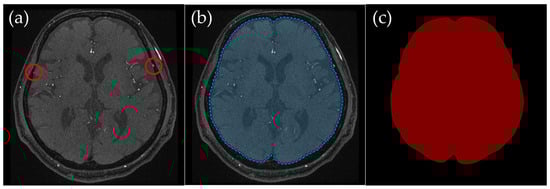

To ensure clarity, ROI creation was tailored to different slice levels, which broadly corresponded to the cranial anatomy from the basal ganglia level of the head down to the skull base. These anatomical levels were selected to systematically exclude non-intracranial structures while preserving the integrity of the cerebrovascular network, ensuring that all critical intracranial vessels were retained while minimizing interference from external carotid branches. Representative examples (Figure 2, Figure 3, Figure 4 and Figure 5) illustrate how the ROIs were manually delineated.

2.3.1. Basal Ganglia Level: Preserving Intracranial Vessels and Removing External Carotid Arteries

Basal Ganglia Level (Figure 2): The external carotid artery branches and other extracranial tissues were excluded, leaving only the brain parenchyma and relevant intracranial vessels. The external carotid artery is particularly problematic in lateral projections, where it can overlap with middle cerebral artery branches, complicating MIP interpretation. This exclusion was crucial to ensuring clear visualization of the middle cerebral arteries in MIP images.

Figure 2. Example of manually annotated training data at the basal ganglia level. (a) Original TOF-MRA axial image (red circles indicate the superficial temporal artery). (b) Manually defined region of interest (ROI) in blue, excluding the external carotid artery and non-intracranial structures. (c) Corresponding indexPNG mask for semantic segmentation training.